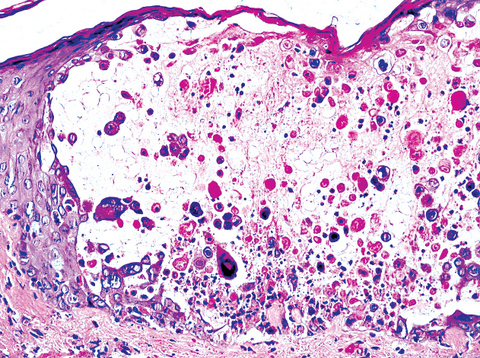

HSV Histology

Multinucleation

Ballooning Degeneration

Tzanck Cells

HSV Histology –> Ballooning Degeneration

Acantholysis (separation of keratinocytes)

Nuclear clearing

Nuclear enlargement

Free floating (clump of cells) epithelial cells

Cells detached

Caused by acantholysis